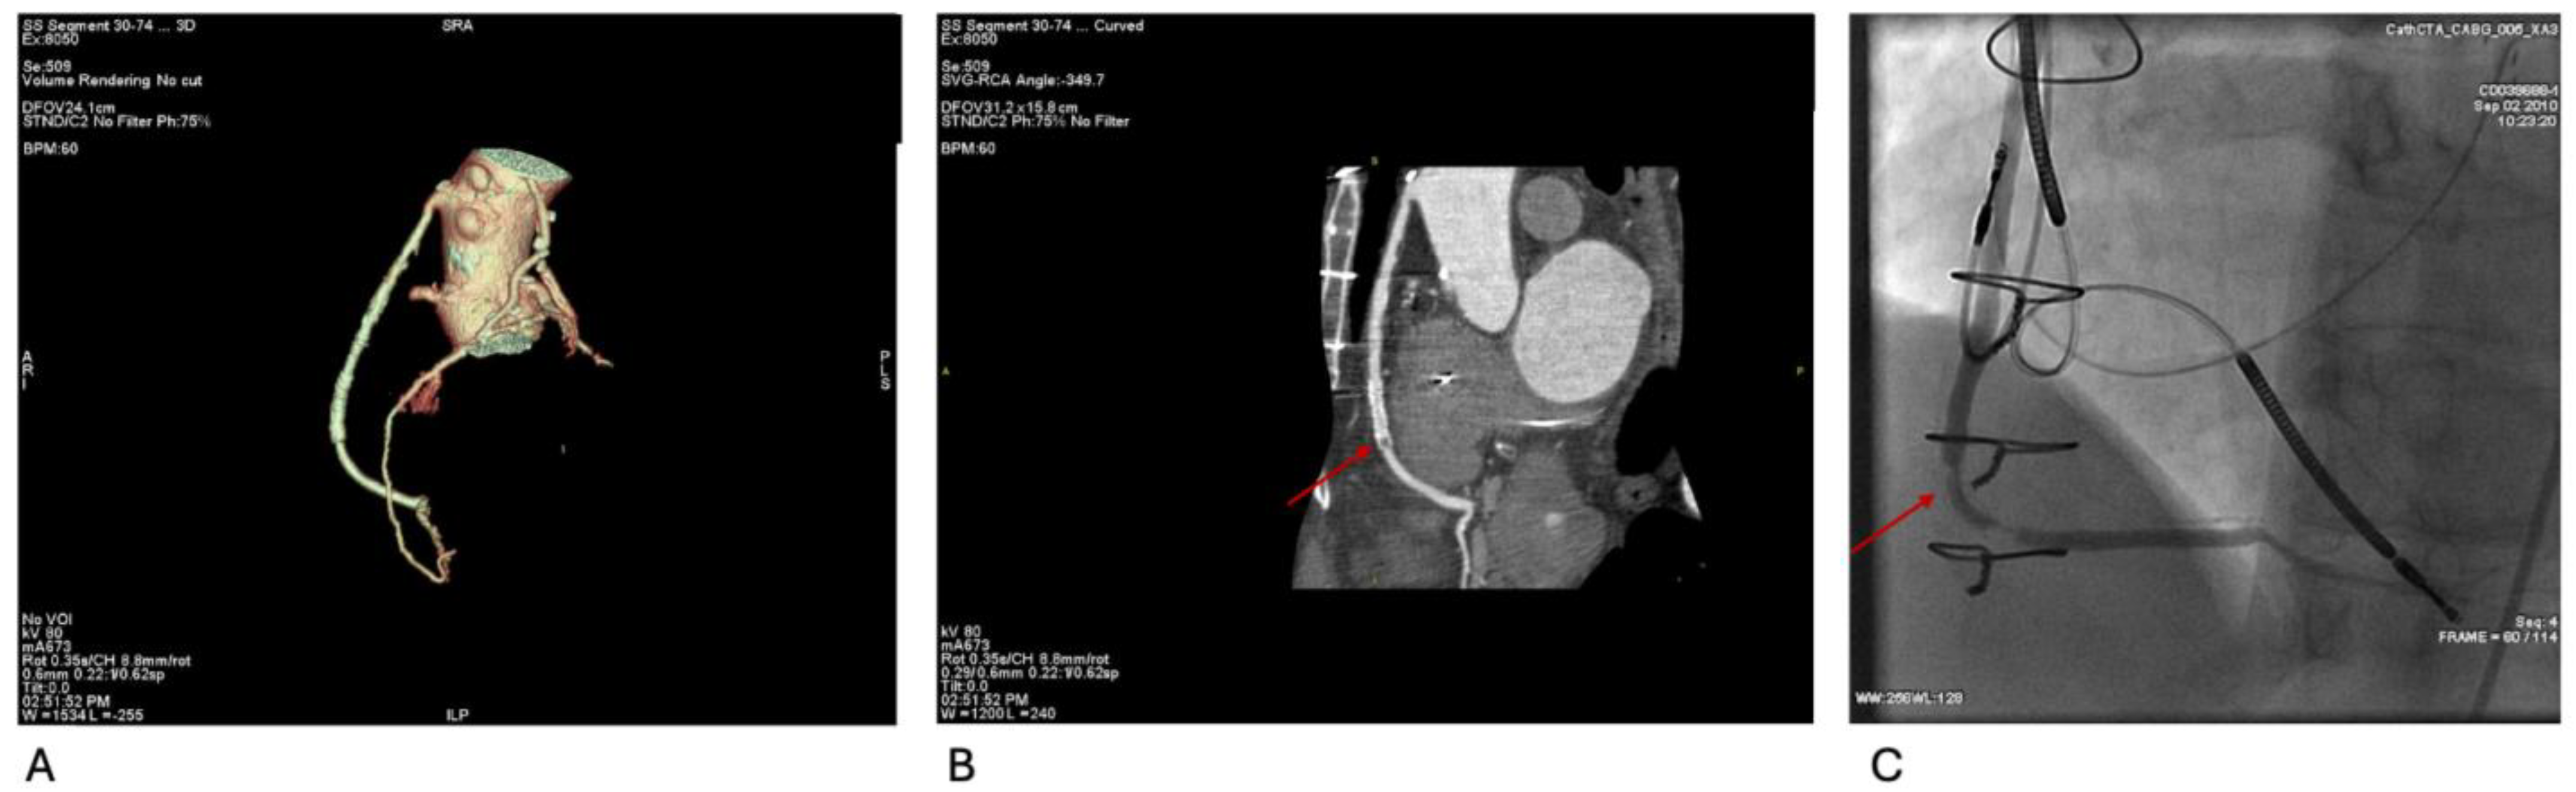

Figure 4A–C illustrate the evaluation of complex CABG anatomy and identification of in-stent restenosis via CCTA and confirmatory angiography. This supports CCTA’s utility in post-revascularization assessment.

Figure 4.

(A) Volume-rendered CCTA demonstrates three-vessel CABG anatomy: LIMA–LAD graft with a sequential saphenous vein graft emerging from the mid-LIMA to a diagonal branch, and a separate saphenous vein graft from the ascending aorta to the right posterior-descending artery (SVG-rPDA). (B) Curved-planar reconstruction of the SVG-rPDA shows a previously deployed stent with marked distal intraluminal hypoattenuation, consistent with in-stent restenosis (arrow). (C) Coronary angiography corroborates severe in-stent restenosis of the SVG-rPDA (arrow).